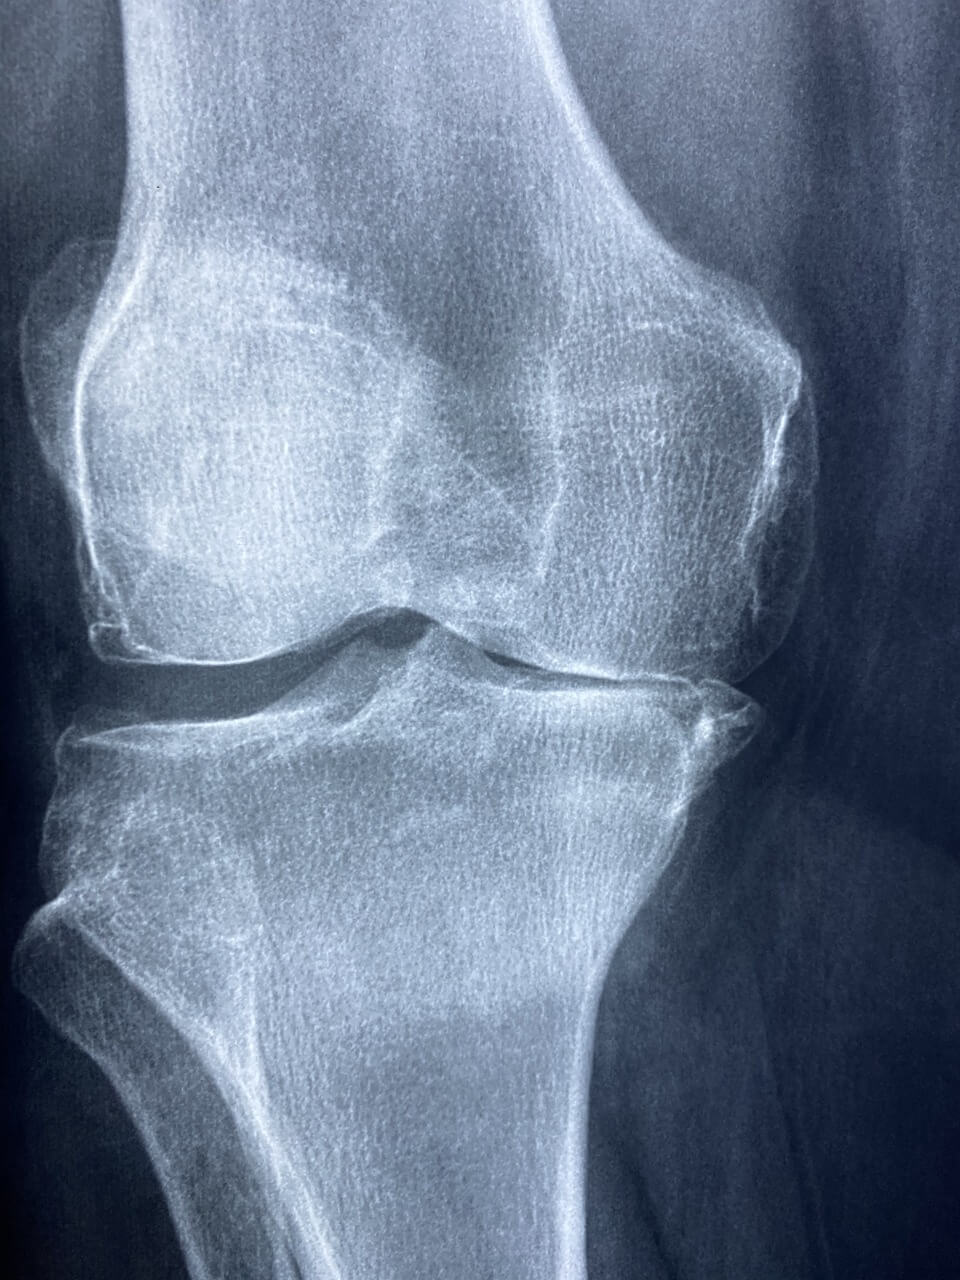

골다공증 검사는 ‘골밀도 검사’라고 불려요. 가장 많이 쓰이는 방법은 DEXA 검사예요.

DEXA 검사는 허리뼈(요추), 엉덩이뼈(대퇴골)를 찍어서 뼈 상태를 확인해요. 누워서 X-ray처럼 찍는 방식이라 통증도 없고 10분 안에 끝나요.